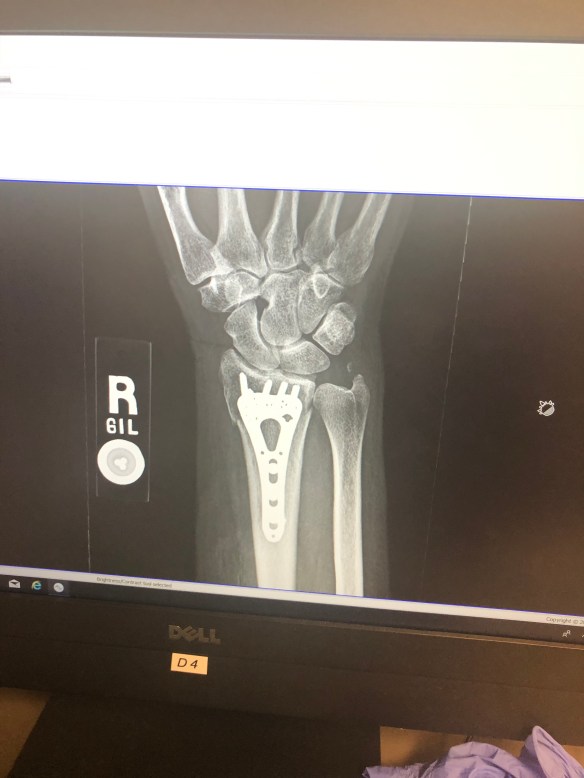

Her wrist is looking pretty good, #amirite?

Under the skin, things look … well … interesting!

That’s what a plate and eight screws look like! And take a look at the little floater of a bone on the right-hand side of the image … that’s break #2 and that one won’t be repaired.